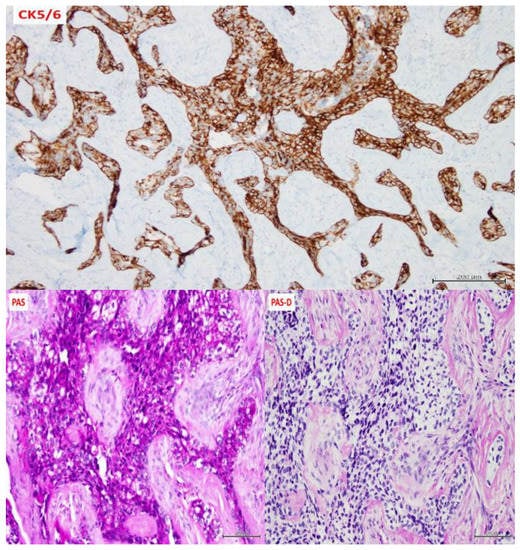

| Staining/IHC | PAS (+) D-labile Mucicarmine (−), p63 (+) CK5/6 (+), CK19 (+) | PAS (+) D-labile Mucicarmine (−) CK5/6 (+) | H&E only |

| Morphology | Infiltrative, non-encapsulated malignant neoplastic odontogenic epithelial proliferation with clear cell component in a dense fibrous connective tissue stroma. Neoplastic cells arranged in anastomosing trabeculae. Nuclear hyperchromasia and pleomorphism surrounded by clear, vacuolated cytoplasm. Stroma was hyalinized, densely collagenized, hypocellular, and hypovascular. | Neoplastic odontogenic epithelial proliferation diffusely infiltrated the connective tissue stroma. Neoplastic cells arranged in islands of variable size, trabeculae, and nests. Nuclei were hyperchromatic, central, and pleomorphic surrounded by clear cytoplasm. | Infiltrative odontogenic epithelial neoplasm intermixed with eosinophilic dentinoid matrix. Neoplastic cells arranged in infiltrative, non-encapsulated sheets, cords, and nests of polygonal cells with central hyperchromatic and slightly pleomorphic nuclei surrounded by clear cytoplasm and occasional pale eosinophilic cytoplasm. Occasional mitotic figures were noted. Neoplastic epithelial sheets and cords blended with eosinophilic cellular matrix without cellular rimming consistent with dentinoid deposits. |